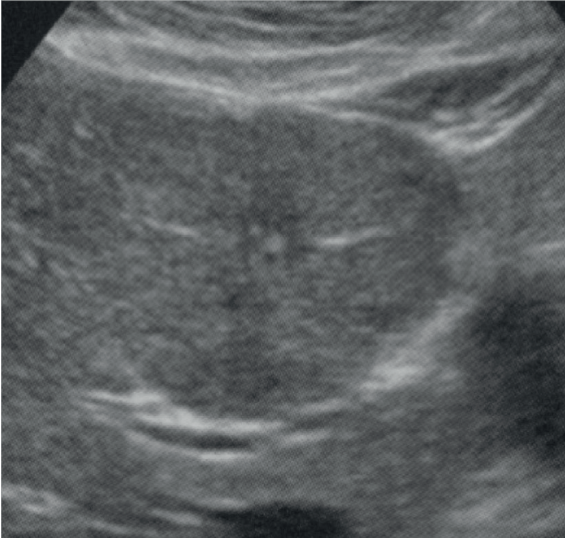

Considerando a imagem acima e as características de hiperplasia nodular focal, é incorreto afirmar que